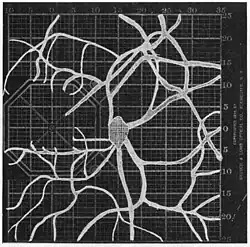

Angioscotomas were first discovered and mapped out by John Norris Evans (1891-02-28--1953-04-08)[2] in 1926, who coined the term angioscotometry to describe the painstaking charting of the scotoma of the retinal blood vessels by manual perimetry. He seated each subject in a seat in a dark setting, and tested whether they could see a tiny bright test object placed at various locations.[3] Using a 1.5 mm white disk, Evans reported intricate branch‑like scotomas that mirrored the arteries and veins emerging from the optic disc, with a full map requiring up to 2 hours to complete. He plotted this for subjects under various conditions, such as while holding breath, with glaucoma, etc. A year later, he confirmed that only short stump‑like scotomas had been noticed previously, some further data plotted with a smaller 1 mm stimuli, and under varying conditions on the subject.[4] He published a monograph on this in 1938 in which he described its use in assisting diagnosis of various conditions, such as retinal edema, glaucoma, optic neuritis, etc.[5]

Using eccentric fixation, the more nasal parts of the angioscotoma can be plotted. -

1. Pressure on globe shows only stumps of large vessels. 2. Holding the breath causes similar effect; also 3. Holding the head low. 4. Pressure on opposite eye widens arteries and still more veins, 5. Pressure on the carotid produces no definite effect. 6. Looking thru red glass brings out finer vessels. -